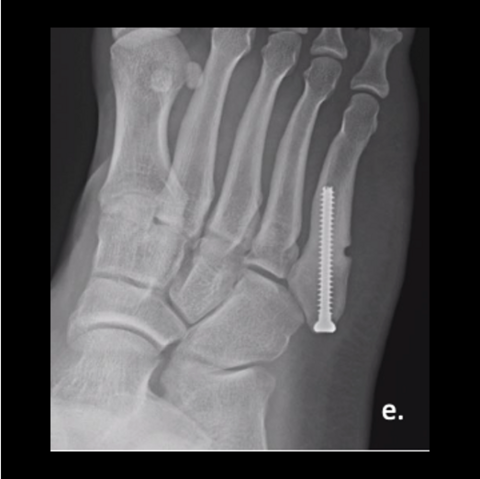

Figure 1e

Figure 1e. We fixed his fracture with an intramedullary, fully-threaded, cannulated 4.5mm screw. He returned to training at 3 months. As shown here, the fracture looked healed at 6 weeks postop.